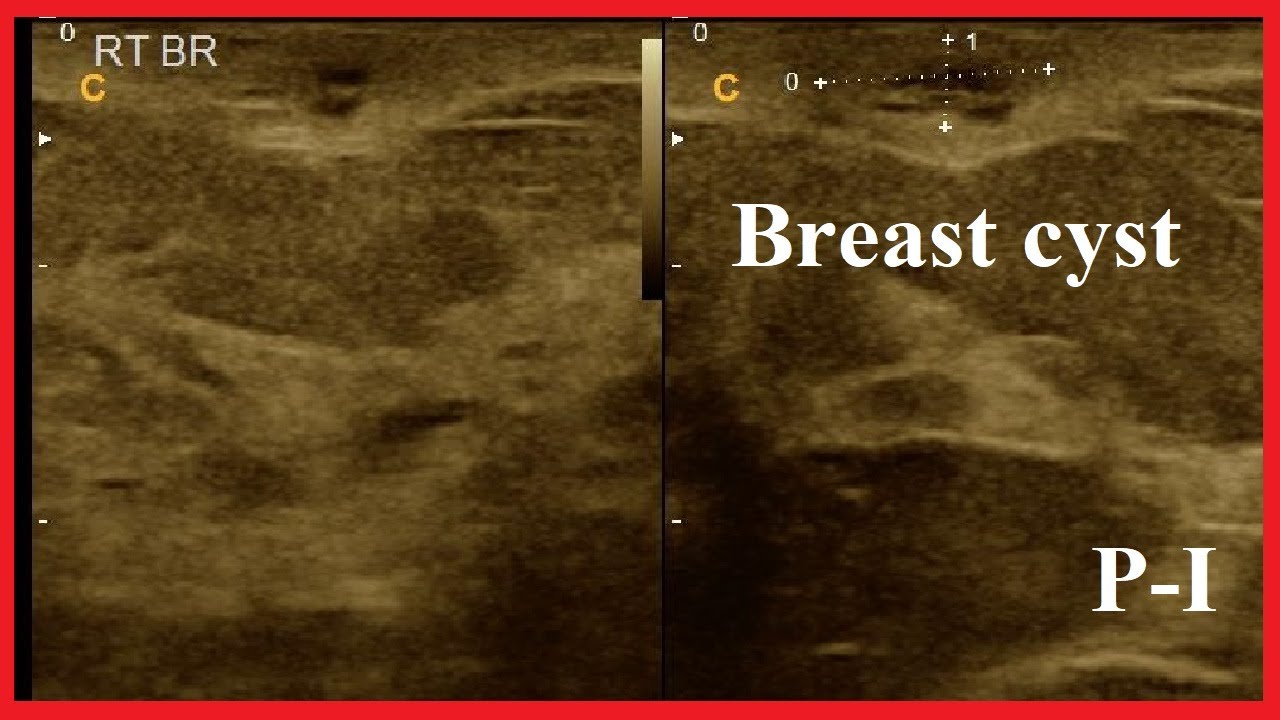

Infected breast sebaceous cyst Critical Care Sonography

a Right breast ultrasound. A 6mm benign cyst can be observed in the Infected Cyst Under Breast not all epidermal inclusion cysts become infected, but infection is possible. Breast abscesses can be a complication. See pictures, discover treatments, and more. it’s possible to develop an abscess following an injury to your chest. if fluid comes out and the breast lump goes away, your doctor can make a breast cyst diagnosis. breast cysts are. Infected Cyst Under Breast.